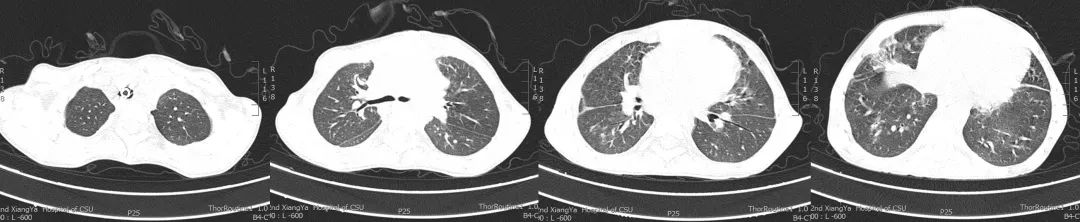

经过临床-康复-护理积极地综合治疗与管理,影像学对比发现:双肺弥漫性渗出灶较前明显吸收,双侧斜裂积液及心包腔内积液稍减少。

图:2019年5月5日CT

图:2019年6月10日CT

客观资料: 肺部体查(视诊:开胸术后、气管切开术后改变;触诊:双侧呼吸动度对称;叩诊:清音;听诊:双肺呼吸音清,未闻及干湿性啰音),氧疗参数(模式:HFNC;氧流量:30L/min;FiO2:25%;温度:34℃),生命体征(T:36.3℃;P:120次/分;R:18次/分;BP:92/57mmHg),实验室检查(WBC:5.39×10^9/L;N%:83.2%;L%:9.8%;HGB:97g/L;PLT:213×10^9/L;CRP:6.95mg/l;PCT:0.25ng/ml;TnI:<0.05ng/ml;BNP:490pg/ml;Mb:119μg/l;CKMB:16.1u/l;D-二聚体:>5000μg/ml;ALT:20.3u/l;AST:26.6u/l;ALB:41.4g/l;BUN:3.82mmol/l;Cr:23.9μmol/l),血气分析(PH:7.405;PCO2:39.6mmHg;PO2:96.8mmHg;HCO3-:25mmol/l;SaO2:97.2%;FiO2:25%;P/F:387.2mmHg)。辅助检查(2019年6月10日CT:双肺弥漫性渗出灶较前明显减少,双侧斜裂积液及心包腔内积液稍减少;下肢血管彩超:双下肢深静脉血流通畅)。

经过临床-康复-护理积极地综合治疗与管理,影像学对比发现:各叶段支气管通畅,双侧胸腔积液及心包腔积液较前减少。

图:2019年7月24日CT